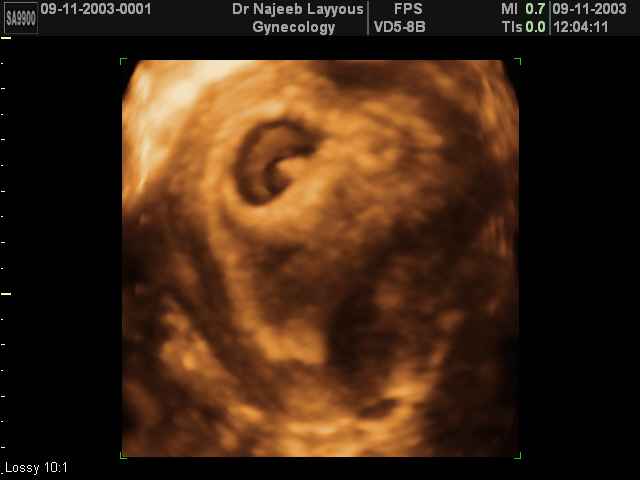

3D First Trimester Ultrasound Scan Photos